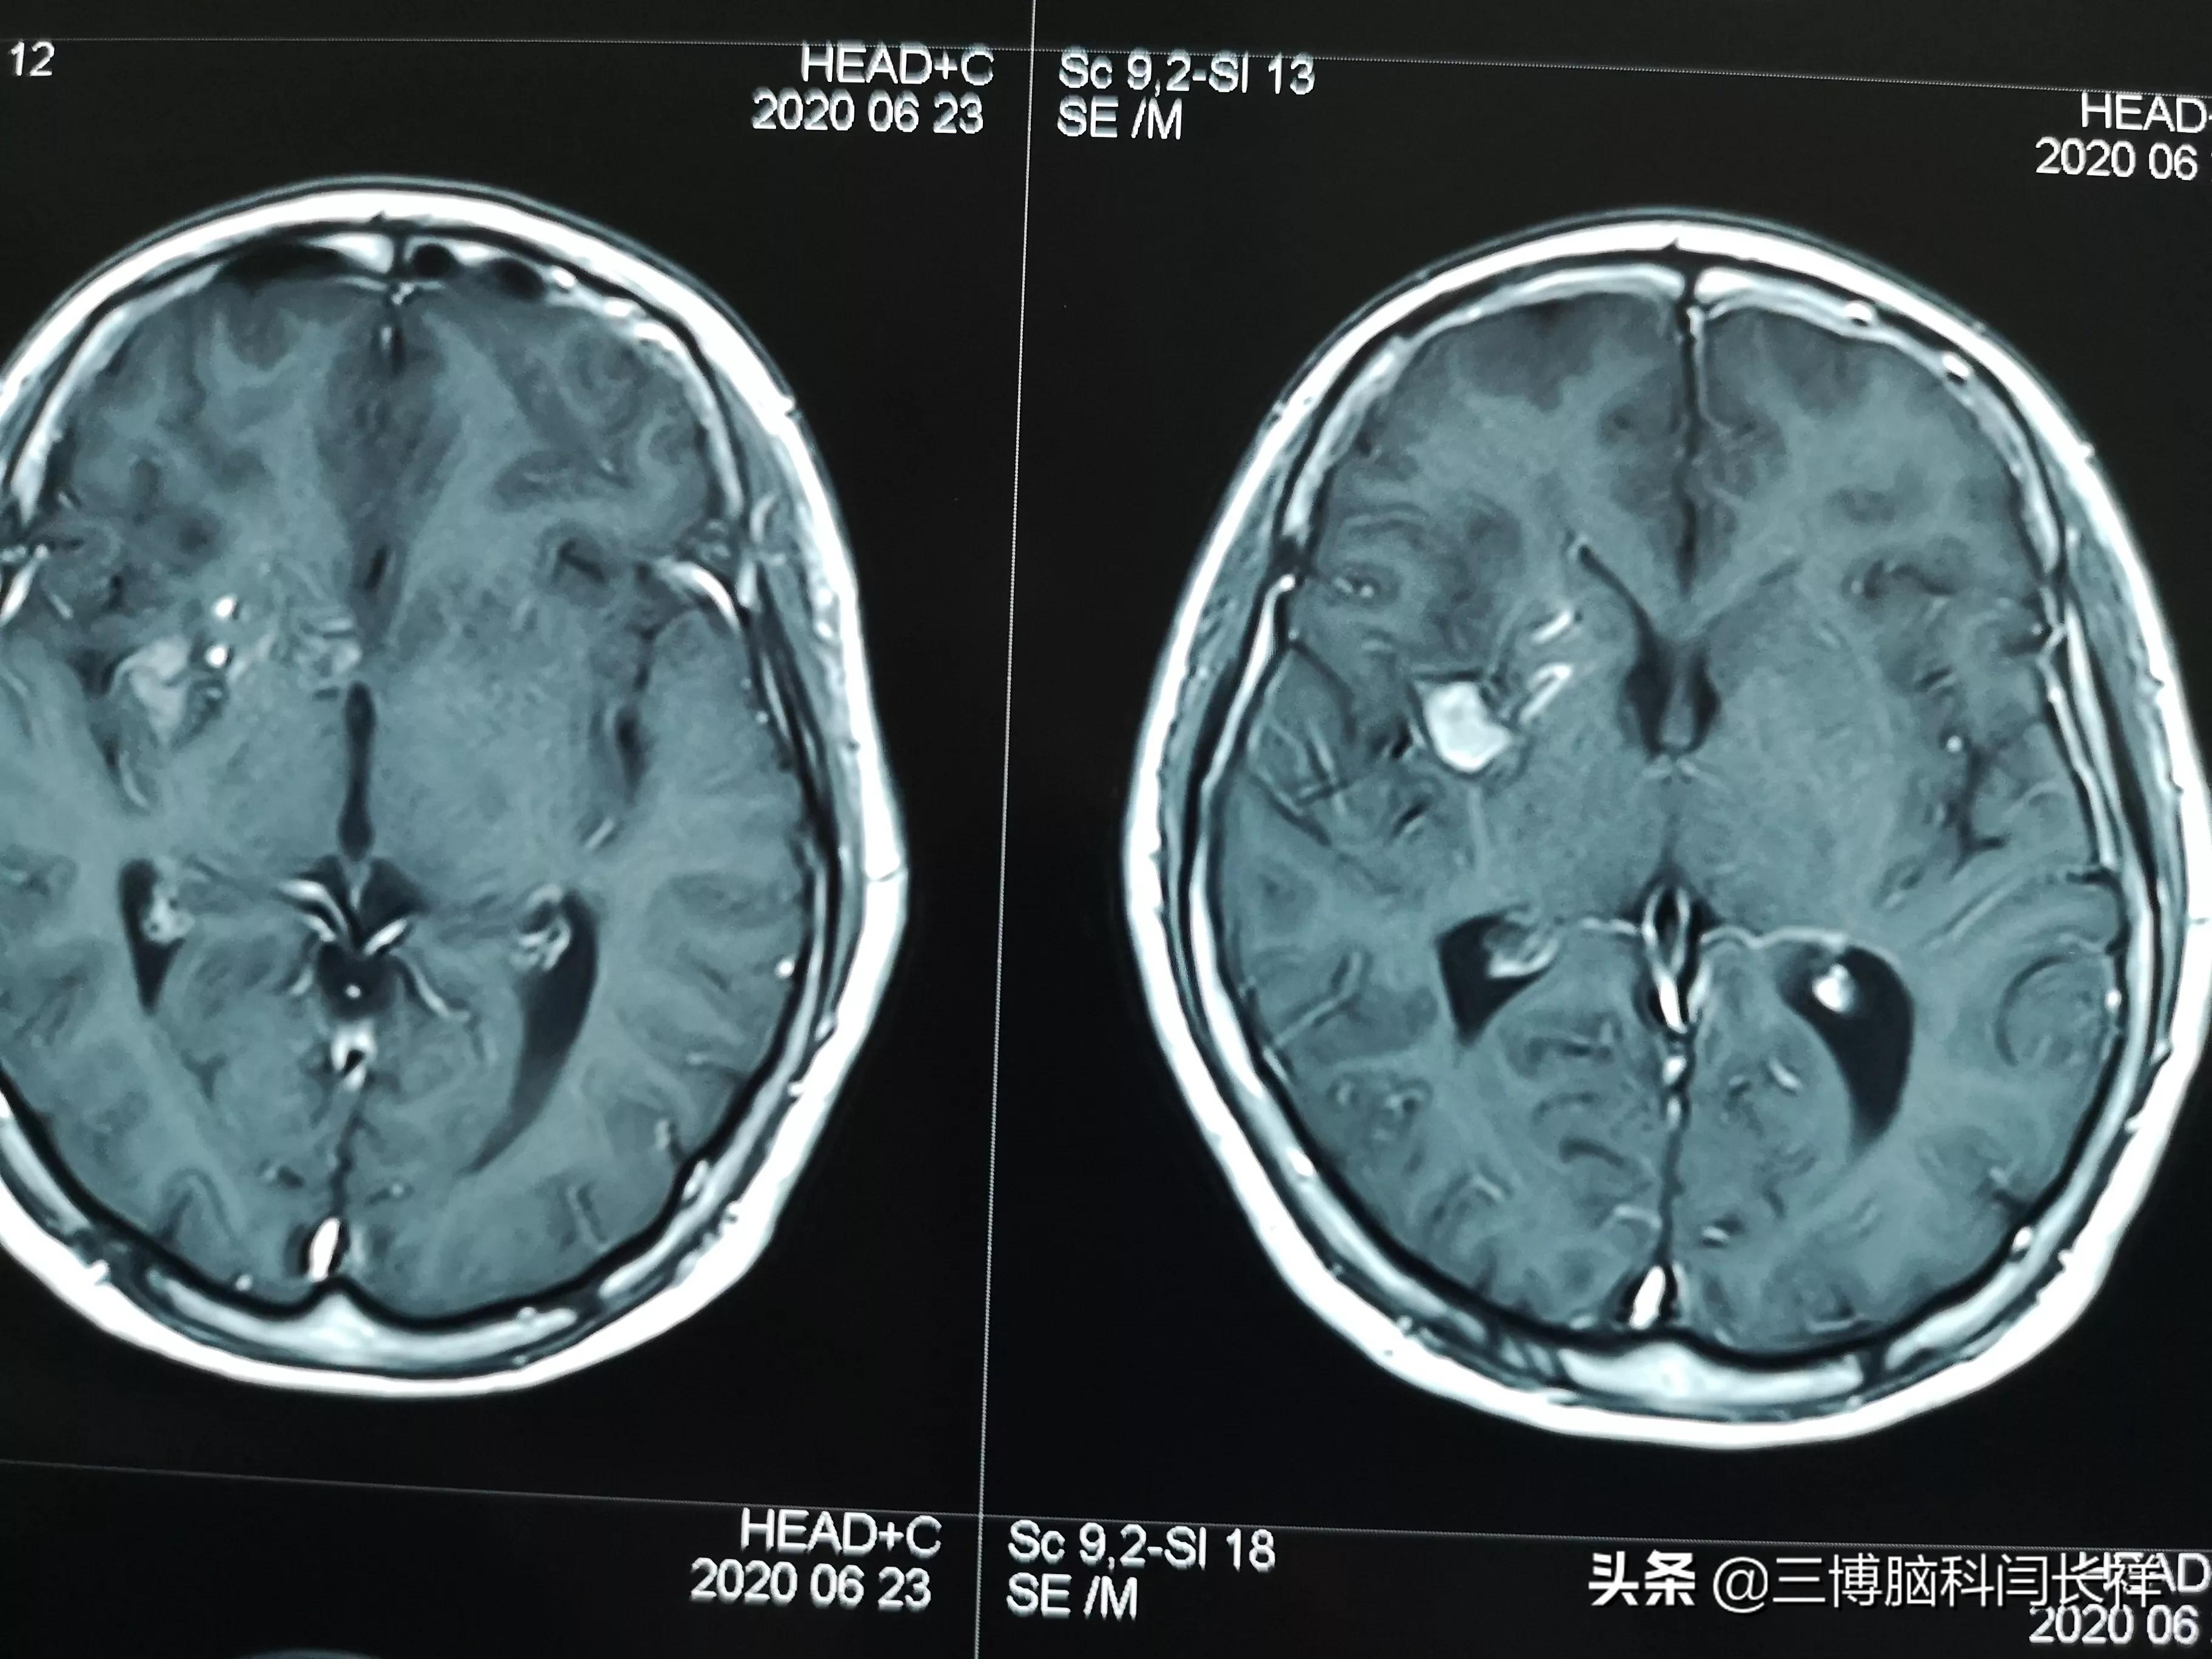

有出血史的脑内海绵状血管瘤要手术_海绵状血管瘤 - 好大夫在线

有出血史的脑内海绵状血管瘤要手术_海绵状血管瘤_海绵状血管瘤治疗